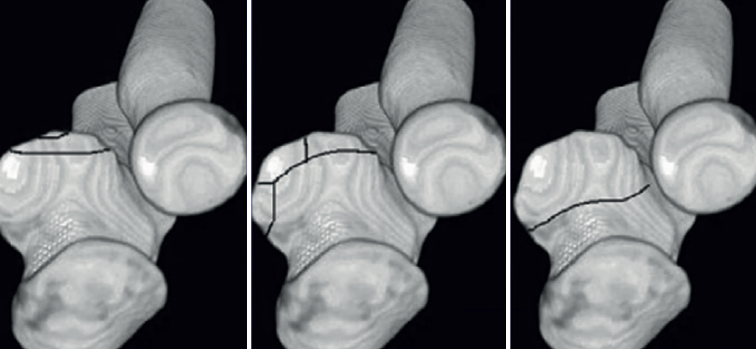

La reducción y la fijación interna de este tipo de fracturas es más sencilla si se realiza antes de la fijación o sustitución de la cabeza radial y de la reparación del LCL, por lo que es importante tener en cuenta si va a ser necesaria la reparación de la apófisis coronoides durante la planificación quirúrgica. Clásicamente, se había utilizado la clasificación de Regan-Morrey para definir este tipo de fracturas; sin embargo, actualmente la clasificación de O’Discroll et al. ofrece una forma más detallada de definirlas, basada en la morfología según la tomografía axial computarizada (TAC)(14). Se divide en los tipos I a III. Las de tipo I son fracturas de la punta, asociadas típicamente a la tríada terrible de codo. Este tipo de fracturas son difícilmente sintetizables por su pequeño tamaño, por lo que se prefiere repararlas con arpones o suturas transóseas de tipo Lasso(15). Es importante destacar también que la necesidad de reparar la coronoides, por pequeño que sea el fragmento, recae en que puede contener la inserción a la cápsula anterior, que proporciona estabilidad en el plano anteroposterior(7).

Las de tipo II son fracturas de la faceta anteromedial, relacionadas con la inestabilidad en varo posteromedial rotatoria, y las de tipo III, de la base de la apófisis, asociadas a fracturas-luxaciones transolecraneanas, son fracturas de mayor tamaño para las que a veces es necesario realizar un abordaje medial y se utilizan en su síntesis, tornillos o placas preconformadas(5-14) (Figura 4).